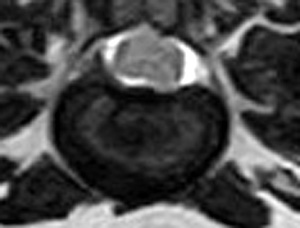

犬の多発性胸腰部椎間板ヘルニアのMRI検査

市外の先生からダックスちゃんの腰の痛みの精査依頼でMRI検査のご紹介がありました。検査結果から多発性胸腰部椎間板ヘルニアを認めました。その後かかりつけの先生のもとで内科治療となりました。